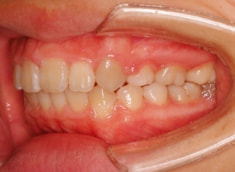

上顎前突ケース

治療法:表の矯正(T21ブラケット)

治療前